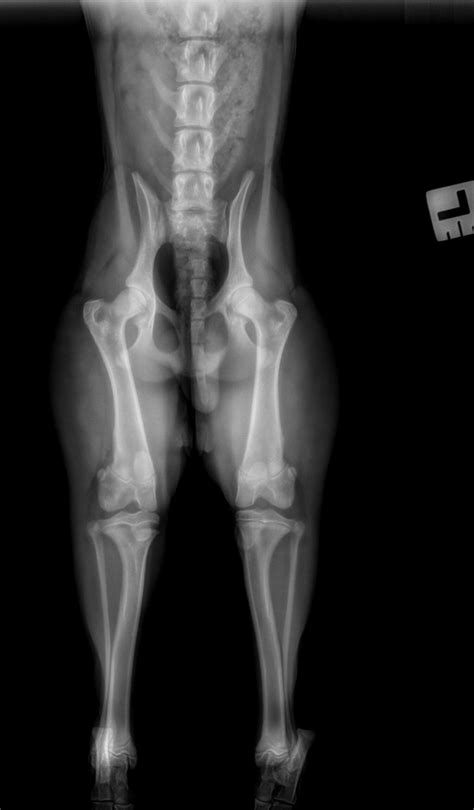

• Monitoring: Periodic X-rays are taken to ensure the bone remains aligned and to monitor for any signs of premature growth plate closure.

The prognosis for a Salter Harris Type II injury is typically very positive. Because the blood supply to the growth plate is generally preserved during this type of fracture, the risk of "growth arrest" or stunted limb development is significantly lower than in other classifications. Most children return to full athletic participation within a few months, provided the rehabilitation process is followed diligently.

However, parents should be aware of "red flag" symptoms during the recovery period. If the child reports increasing pain, numbness, or if the limb appears to be growing at a different rate than the non-injured side over the following months, a follow-up consultation with a pediatric orthopedic surgeon is essential.